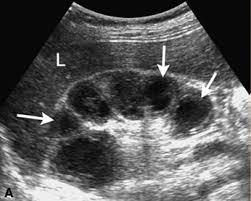

30 year old male presents for a renal ultrasound

liver & spleen cysts

Adult Polycystic Kidney Disease